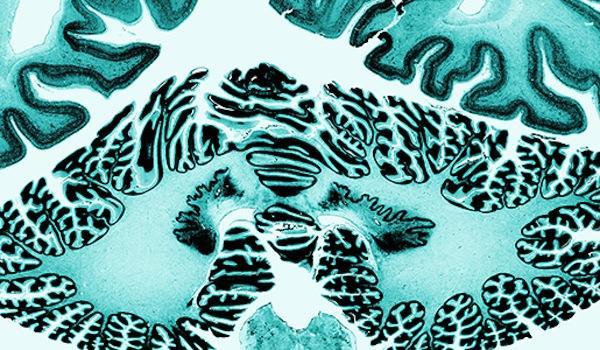

Tra i temi dell'esame di maturità, quest'anno spiccava il cervello. Negli stessi giorni, la rivista scientifica Science annunciava la realizzazione della prima mappa in 3 dimensioni di questo organo. Per ottenerla i ricercatori hanno sezionato il cervello di una donna deceduta, in più di 7 mila fettine di 20 micrometri di spessore. Questo risultato permetterà di studiare la forma e le funzioni del nostro cervello in modo estremamente approfondito. Le neuroscienze si confermano in questo momento la disciplina di maggior successo nel mondo scientifico e nell'interesse dei media.